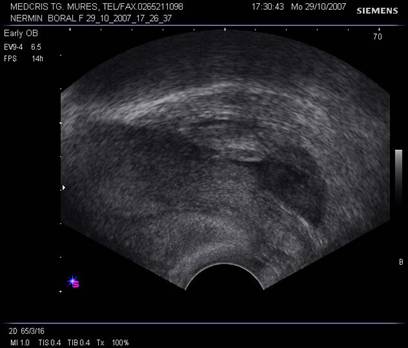

Fig nr 64.

Endometru ingrosat (marcat cu sageata, de fapt decidualizat ) fara sac gestational intrauterin, la pacienta cu

embrion cu activitate cardiaca situat intratubar.